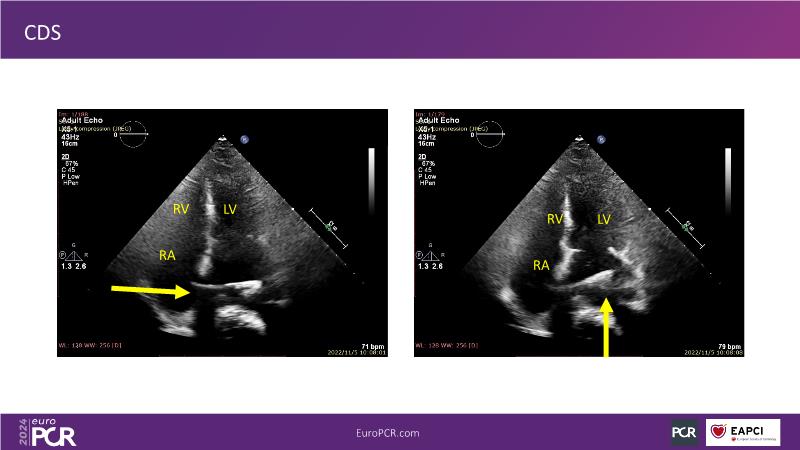

Watch this session to gain insights into the clinical evidence of mitral TEER therapy for the Asian population, learn techniques for implanting a MitraClip in patients with challenging anatomy, and understand how to use the four clip sizes for optimal outcomes. The session also covers educational aspects of clipping in dextrocardia, the benefits of reserve bending of the transseptal needle for tenting and puncture, new steering maneuvers for dextrocardia patients, and the importance of understanding anatomy and collaborating closely with the echo team for success.